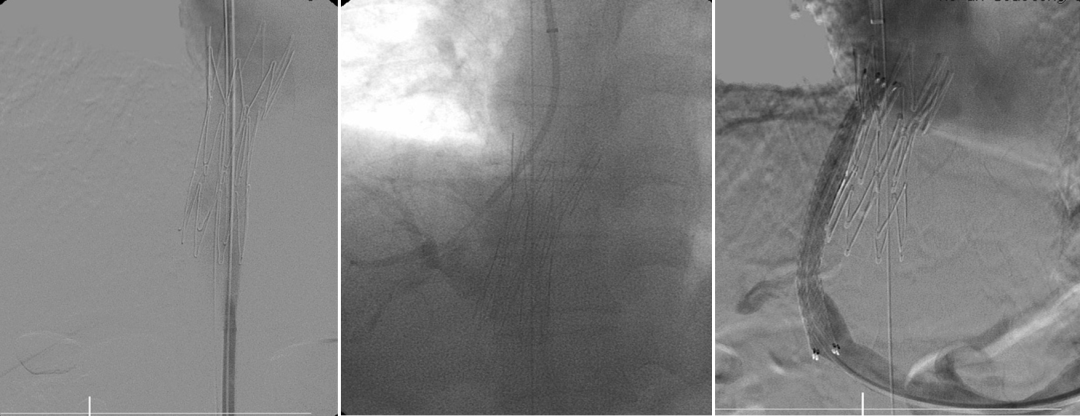

栓塞材料与再干预技术

栓塞剂从早期的泡沫硬化剂、无水酒精、弹簧圈,发展到如今的生物组织胶,止血更彻底;

泡沫硬化剂—无水酒精—弹簧圈—生物组织胶

Viatorr覆膜支架的应用

针对分流道再狭窄或再出血,创新应用平行支架技术,并通过体外模拟验证支架扩张可行性;

平行支架技术

TIPS术后再出血,胃底静脉栓塞+平行支架

经皮经肝导丝引导穿刺门静脉左支,血管塞栓塞异常分流道及胃底曲张静脉

弹簧圈联合血管塞+组织胶栓塞异常分流道